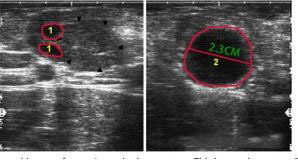

On Day 0 of estrus synchronization protocol, a transrectal ultrasound scan was performed on a multiparous Holstein cow. The images revealed the following:

Left Ovary: Two small follicles measuring 0.5 cm each were visible. No clear CL was detected, although the ovarian stroma appeared slightly heterogeneous, possibly masking a regressing CL.

Right Ovary: A single dominant follicle measuring 2.3 cm was identified. It exhibited a round, anechoic appearance with a smooth wall—typical characteristics of a preovulatory follicle.

This image confirmed the cow was in the late pre-estrus phase, making her an excellent candidate for AI within 24 to 36 hours.